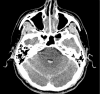

Figure 1:

Axial plane of non-contrast cranial computed tomography scan on admission. The study revealed the presence of infratentorial subarachnoid hemorrhage, as well as ventricular irruption, with evidence of bleeding in the fourth ventricle.